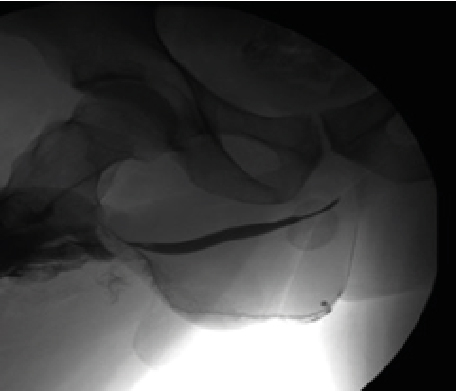

Retrograde urethrography is a very dynamic study, which must be taken into account when acquiring images, especially when sending still images, a common error is the leakage of contrast towards the skin (Figure 1) avoiding using a Foley catheter at the level of distal urethra to retain the contrast, however it can condition trauma [1]. Another common error is the ignorance of ideal projections for evaluation of the urethra (Figure 2), for example the Lauenstein projection, which is more useful for evaluating the hip. The imaging with a lack of contrast between the structures (Figure 3), which can be modified during and after the acquisition. It should be noted that on some occasions, in case of doubt, images will be taken from two different x-ray directions.

Figure 1: Contrast Drainage in Skin, Can Simulate Double Urethra or False Via